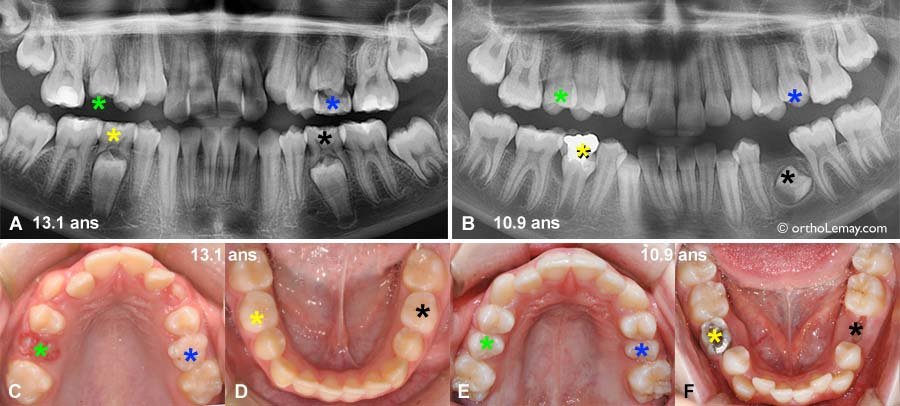

La chronologie de ce phénomène varie selon les dents, suivant généralement l’ordre d’éruption initial : incisives centrales mandibulaires en premier (vers 6-7 ans), puis progression vers les secteurs postérieurs jusqu’aux secondes molaires temporaires (vers 10-12 ans).

La connaissance approfondie de ces trois stades physiologiques permet d’établir un diagnostic précis et d’adapter les protocoles thérapeutiques. L’examen radiologique constitue un complément indispensable à l’examen clinique.